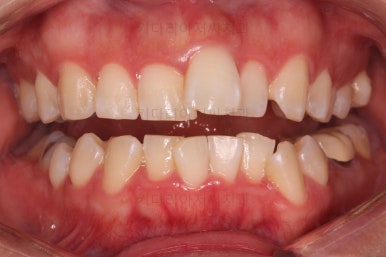

초진 시 입안의 모습입니다.

전반적으로 치열이 삐뚤고, 특정 앞니는 톡 튀어나가 미적으로 좋지 못한 상황이었습니다.

이갈이, 이악물기 습관도 있어서 앞니는 삐뚤어진 채로 치아가 많이 갈려있는 상황이었습니다.